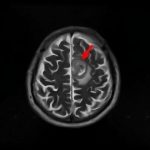

'14年10月

40代

海綿状血管腫

No.’14_160 手術前1

No.’14_160 摘出 前

No.’14_160 摘出 後